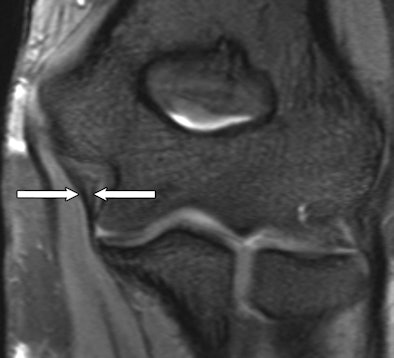

| Coronal 3D MR image of an anterior ulnar collateral ligament (UCL) obtained with TrueFISP in a 27-year-old woman. The anterior UCL (arrows) has a striated signal intensity pattern. Images courtesy of Radiology. |